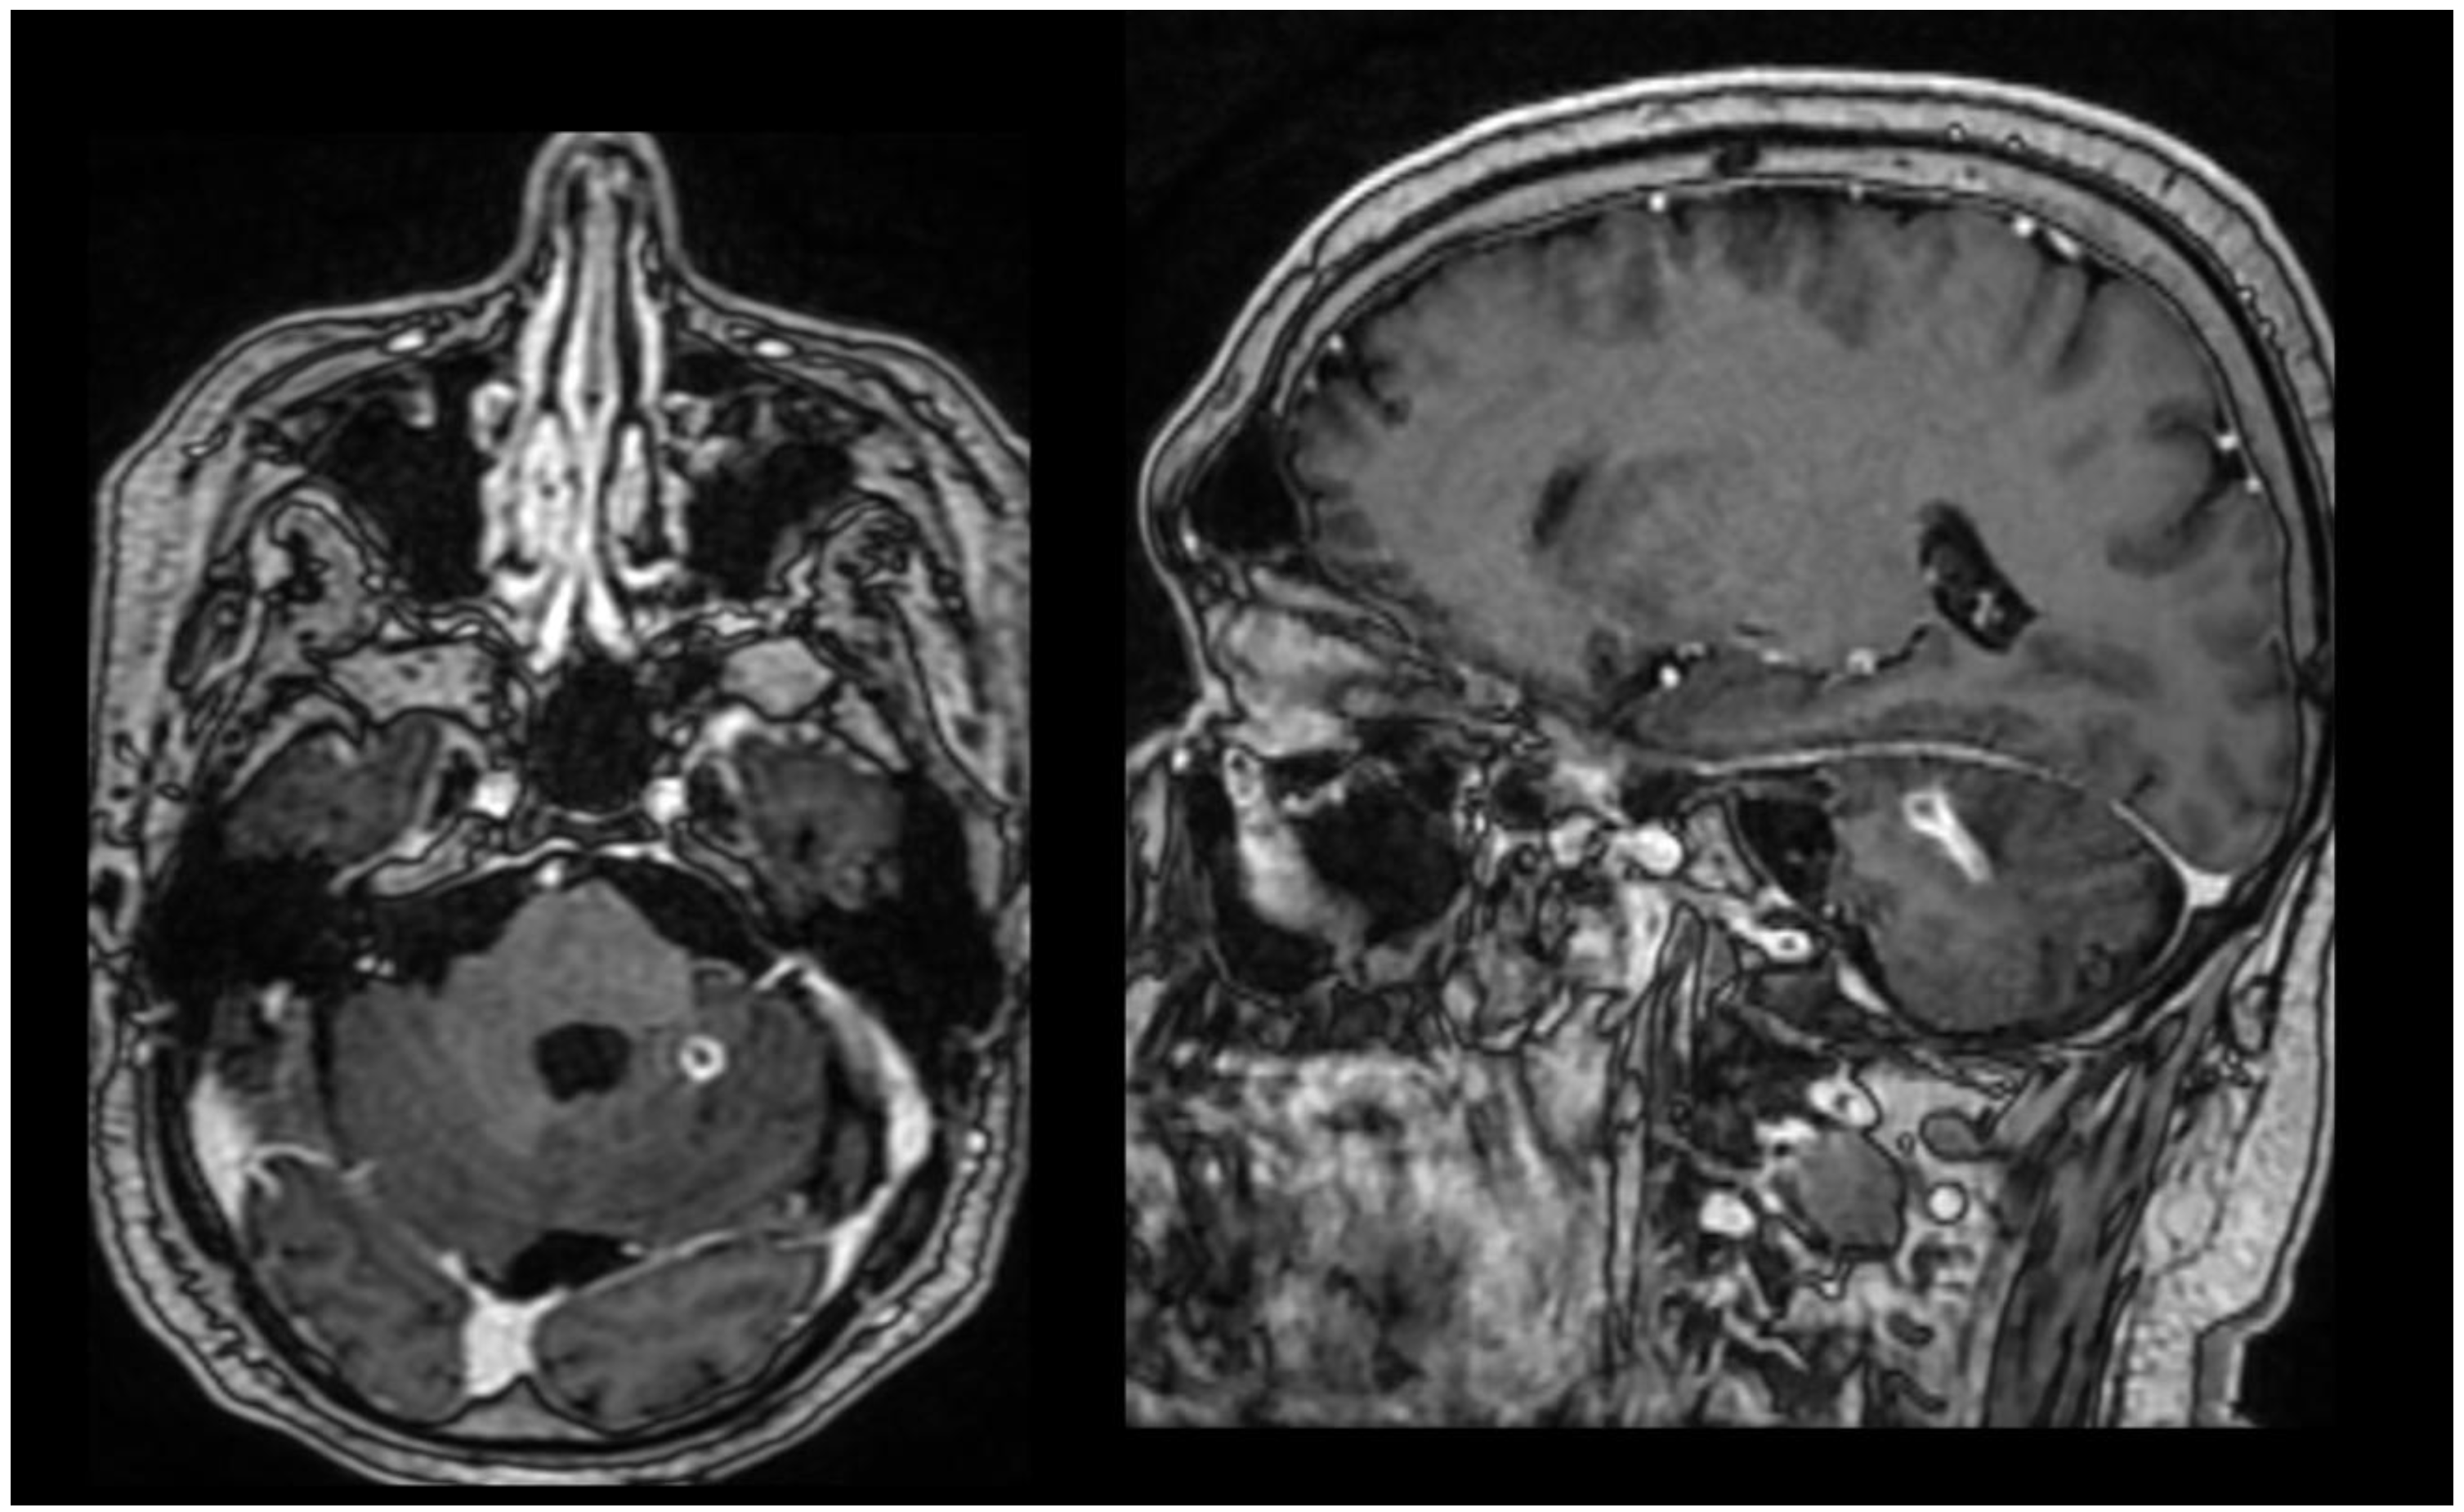

One week before discharge, the brain MRI (Figure 2) showed a postoperative meningocele unchanged compared to the previous examination, occipital craniectomy, and a lesion in the left cerebellar hemisphere, imaging-compatible with an abscess, relatively stable in size compared to the prior study, with chronic inflammatory changes in the bilateral maxillary sinuses.

Figure 2.

Brain MRI one week before discharge in axial and sagittal section.